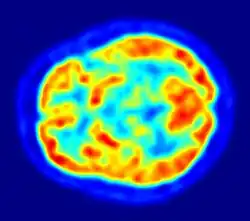

PET Imagem do encéfalo humano mostrando o consumo de energia.

Apesar do cérebro representar apenas 2% da massa corporal, ele é responsável por 20% de consumo total de oxigênio do corpo humano.[40]